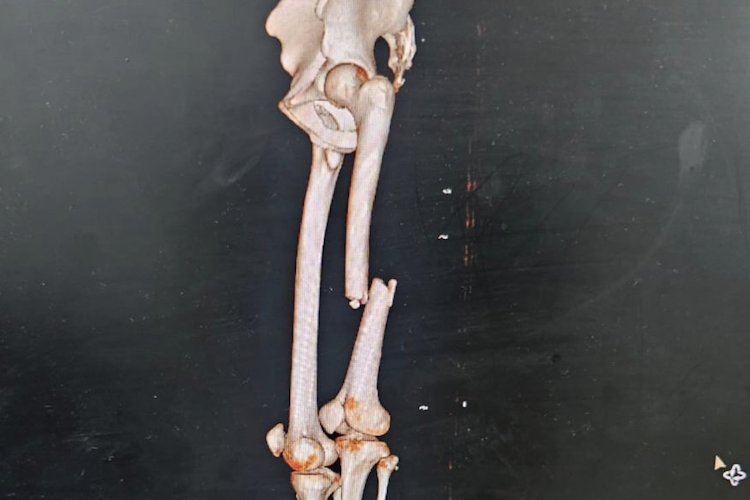

Munoz wurde dann mit dem Hubschrauber nach Mataram geflogen, der Hauptstadt von Lombok. Weil das linke Bein stark geschwollen war, der gebrochene Knochen ist um 3,5 cm verschoben, konnte Munoz nicht sofort operiert werden, sondern erst am Montag. An eine Rückkehr in seine spanische Heimat war nicht zu denken, denn in diesem Zustand kann Munoz in kein Linienflugzeug steigen.

«David wurde gestern operiert – ihm geht es den Umständen entsprechend gut», sagte Intact-Teammanager Peter Öttl im Gespräch mit SPEEDWEEK.com. «Der Knochen wurde mit einem Markstift fixiert. Morgen darf er mit Krücken gehen und am Freitag darf er auch das gebrochene Bein belasten. Vielleicht kann er bis zum Wochenende das Krankenhaus verlassen, dann werden wir einen Heimflug organisieren.»